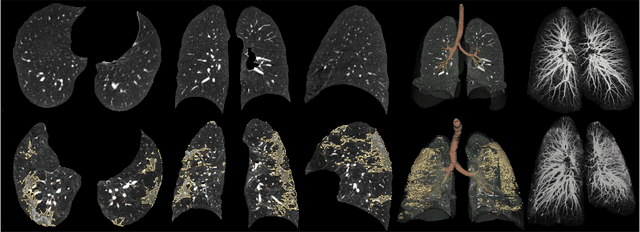

Abstract:Automated segmentation of lung abnormalities in computed tomography is an important step for diagnosing and characterizing lung disease. In this work, we improve upon a previous method and propose S-MEDSeg, a deep learning based approach for accurate segmentation of lung lesions in chest CT images. S-MEDSeg combines a pre-trained EfficientNet backbone, bidirectional feature pyramid network, and modern network advancements to achieve improved segmentation performance. A comprehensive ablation study was performed to evaluate the contribution of the proposed network modifications. The results demonstrate modifications introduced in S-MEDSeg significantly improves segmentation performance compared to the baseline approach. The proposed method is applied to an independent dataset of long COVID inpatients to study the effect of post-acute infection vaccination on extent of lung findings. Open-source code, graphical user interface and pip package are available at https://github.com/MICLab-Unicamp/medseg.